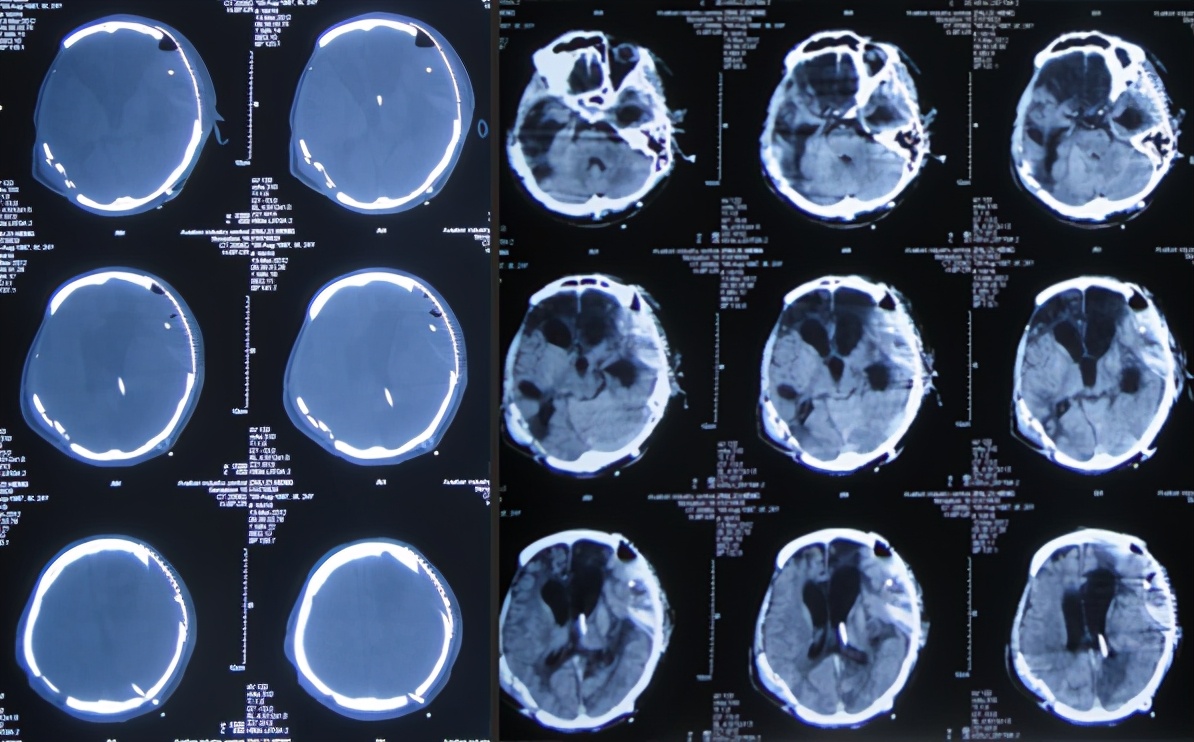

第4家医院治疗87天即开颅术后289天即2011年10月31日,因脑积水始终未得到满意治疗;期间还外请更高级的北京某三甲知名医院的专家会诊,但此专家看完头颅CT后( 图-8 )建议暂时不做腹腔分流术,因为他断定:“做了分流术之后,患者也不可能好转!”。

图-8: 2011年10月31日头颅CT